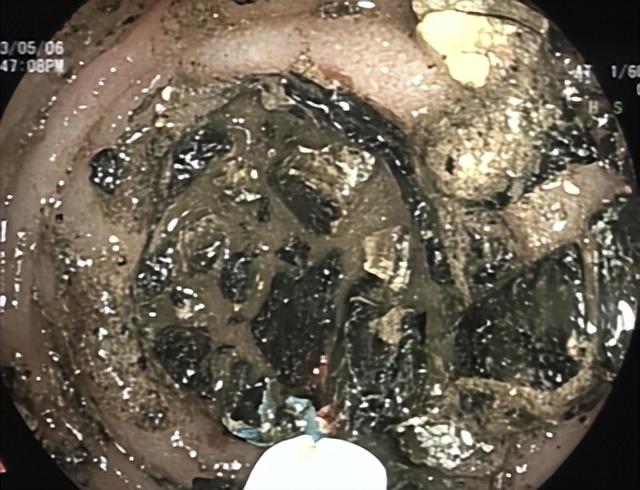

2023年5月6日和8日,哈医大一院群力院区消化内镜中心凭精湛的手法,耐心细致的操作,分次将嵌顿在十二指肠结石全部击碎,复查胃镜十二指肠肠腔通畅,无结石残留(图3、4),于爷爷终于又可以恢复正常生活了。

图3